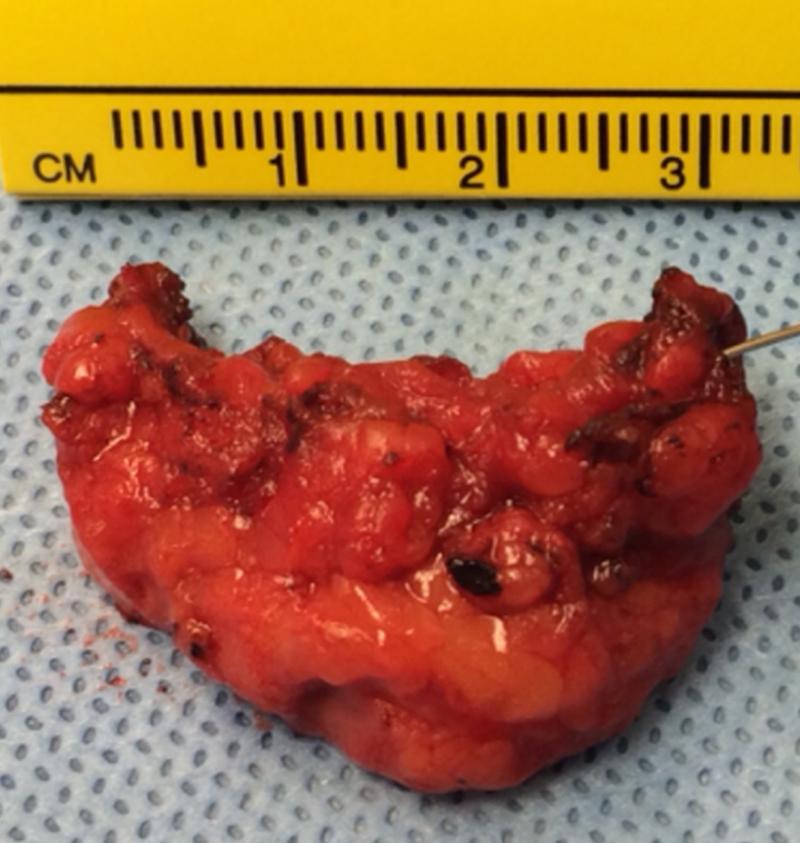

A 20-year-old female presented with a recurrent left breast cyst. Previous aspirations showed no malignancy. Ultrasonography showed a lobulated anechoic lesion with internal debris and thin septations. The patient then underwent a lumpectomy of the left breast cyst, and pathology showed lymphangioma.

Cystic lymphangiomas of the breast are benign lymphatic malformations. Consistent with the main drainage pattern of the breast, cystic lymphangiomas are typically located in the upper, outer quadrant, tail of Spence, and subareolar area. Radiologic evaluation may include ultrasound, mammogram, and MRI. FNA cytology and core biopsy assist in the diagnosis of breast lymphangioma. Although different treatment options exist, complete surgical excision remains the most effective treatment modality for adult cystic lymphangioma of the breast.

Breast cystic lymphangioma is an extremely rare condition, especially in the upper, inner quadrant of the breast. The patient had multiple recurrences of the lesion after fine needle aspirations. Proper index of suspicion, prompt diagnosis, and definitive treatment is necessary to prevent recurrence and complications.